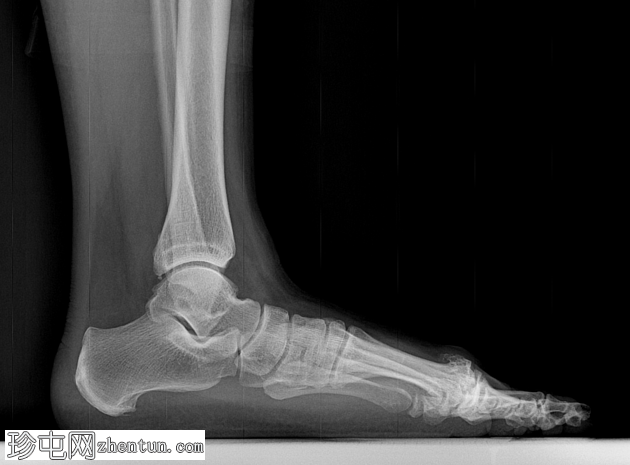

X线片

正位

第一跖趾关节可见巨大骨赘,关节间隙变窄。

斜位片能更清晰地显示关节间隙变窄。

第一跖骨头背侧可见巨大骨赘。

拇外翻是足部最常见的骨关节炎类型。

拇外翻的特征是骨赘形成和关节僵硬,并伴有第一跖趾关节背屈进行性受限。

拇外翻可采用 Coughlin 和 Shurnas 分级法进行分级:

1 级:轻度关节间隙狭窄

2 级:中度关节间隙狭窄伴骨赘形成

3 级:重度关节间隙狭窄伴广泛骨赘形成

4 级:与 3 级相同,但在被动背屈中段出现疼痛

本病例被归类为 Shurnas 4 级。